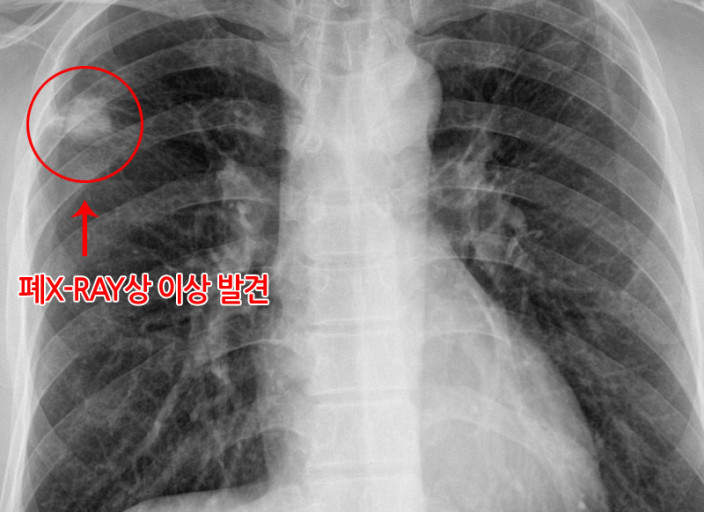

- 즉시 병원 방문: 감기 증상이 3~4일 이상 지속되거나, 고열, 호흡 곤란 등 심각한 증상이 나타나면 즉시 병원을 방문하여 정확한 진단과 치료를 받아야 합니다.